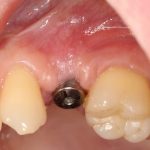

Далее, можем приступить к установке имплантатов. Разумеется. по хирургическому шаблону:

Последняя картинка даёт представление о том, какой объем костной ткани мы «нарастили».